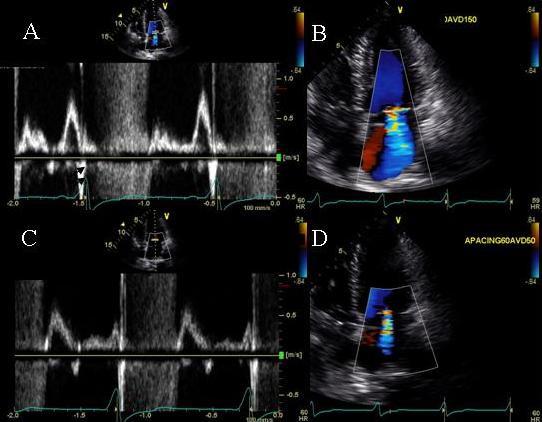

In this report we describe novel therapeutic uses of echo pulsed wave Doppler in atrioventricular pacemaker optimization in patients who had either not derived significant symptomatic benefit post biventricular pacemaker implantation or deteriorated after deriving initial benefit. In these patients atrioventricular optimization showed novel findings and improved cardiac output and symptoms.

In 3 patients with Cheyne Stokes pattern of respiration echo Doppler showed worsening of mitral regurgitation during hyperpneac phase in one patient, marked E and A fusion in another patient and exaggerated ventricular interdependence in a third patient thus highlighting mechanisms of adverse effects of Cheyne Stokes respiration in patients with heart failure. All 3 patients required a very short atrioventricular delay programming for best cardiac output. In one patient with recurrent congestive heart failure post cardiac resynchronization, mitral inflow pulse wave Doppler showed no A wave until a sensed atrioventricular delay of 190 ms was reached and showed progressive improvement in mitral inflow pattern until an atrioventricular delay of 290 ms. In 2 patients atrioventricular delay as short as 50 ms was required to allow E and A separation and prevent diastolic mitral regurgitation. All patients developed marked improvement in congestive heart failure symptoms post echo-guided biv pacemaker optimization.

在3例患有陈 - 施呼吸模式的患者中,回声多普勒显示,1例患者在呼吸急促阶段二尖瓣反流恶化,另1例患者出现明显的E峰和A峰融合,第3例患者存在过度的心室相互依赖,从而突出了陈 - 施呼吸对心力衰竭患者产生不良影响的机制。所有3例患者都需要非常短的房室延迟程控来获得最佳的心输出量。在1例心脏再同步治疗后反复出现充血性心力衰竭的患者中,二尖瓣流入脉冲波多普勒显示,在感知到的房室延迟达到190毫秒之前没有A波,并且在房室延迟达到290毫秒之前二尖瓣流入模式逐渐改善。在2例患者中,需要短至50毫秒的房室延迟来实现E峰和A峰分离并防止舒张期二尖瓣反流。所有患者在回声引导下进行双心室起搏器优化后,充血性心力衰竭症状均有明显改善。